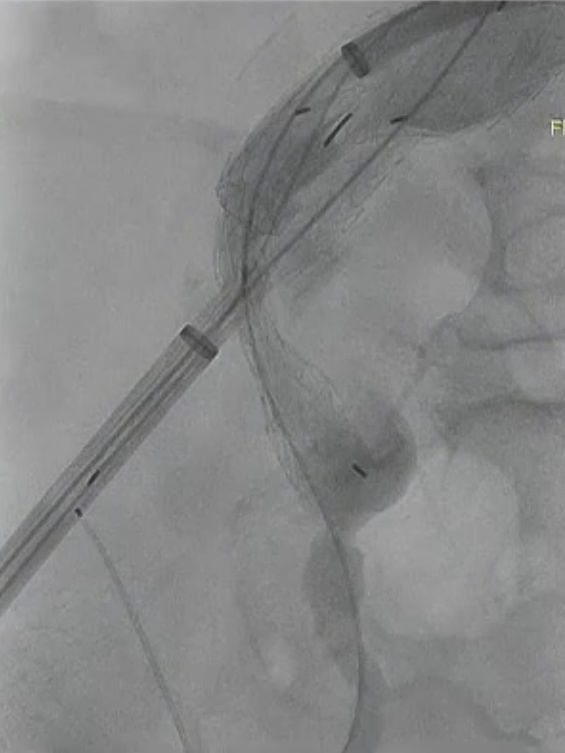

病例2:巨大扭曲动脉瘤的复合治疗策略

诊断:72岁男性,EVAR术后髂动脉瘤伴髂内动脉瘤。

手术过程:肱动脉入路,连接长主体与近端腹主支架,髂内搭配VBX并备弹簧圈。术中遇到挑战,髂内动脉瘤大且扭曲,导致VBX输送困难,支架长度略短,术后造影出现内漏。通过股动脉入路,经支架远端-血管壁之间进入髂总,进行弹簧圈栓塞,促进血栓化。

术后情况:后续随访观察,术后效果良好,动脉瘤得到有效处理,髂内动脉血流通畅。